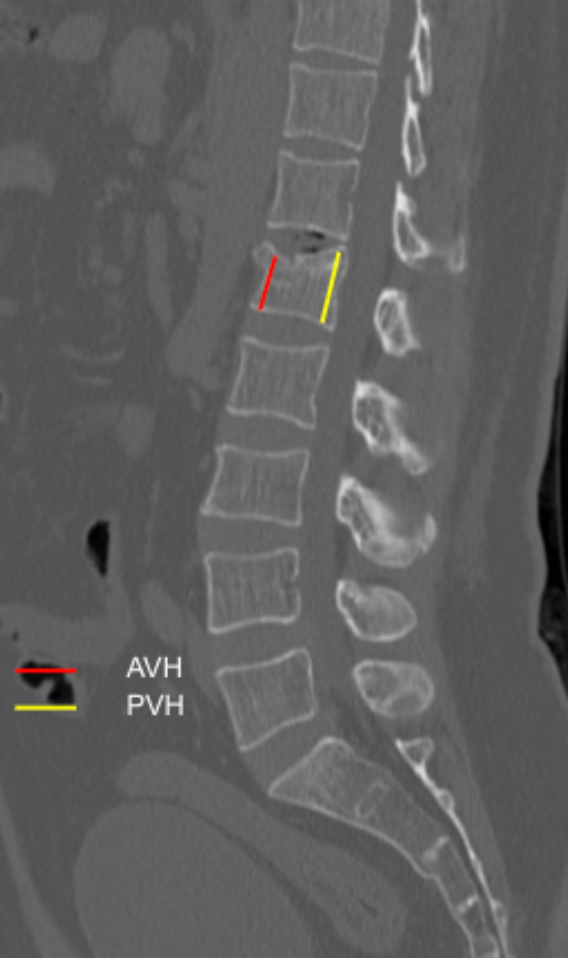

The Sagittal Index (SI) quantifies vertebral body wedge deformity in compression fractures by comparing the anterior vertebral body height (AVH) to the posterior vertebral body height (PVH) on sagittal CT images. This ratio reflects the degree of anterior column collapse and correlates with fracture severity, kyphotic deformity, and instability risk.

• Anterior Vertebral Height (AVH): Distance between the superior and inferior anterior vertebral endplates.

• Posterior Vertebral Height (PVH):

Distance between the superior and inferior posterior vertebral endplates.

Sagittal Index = AVH/PVH